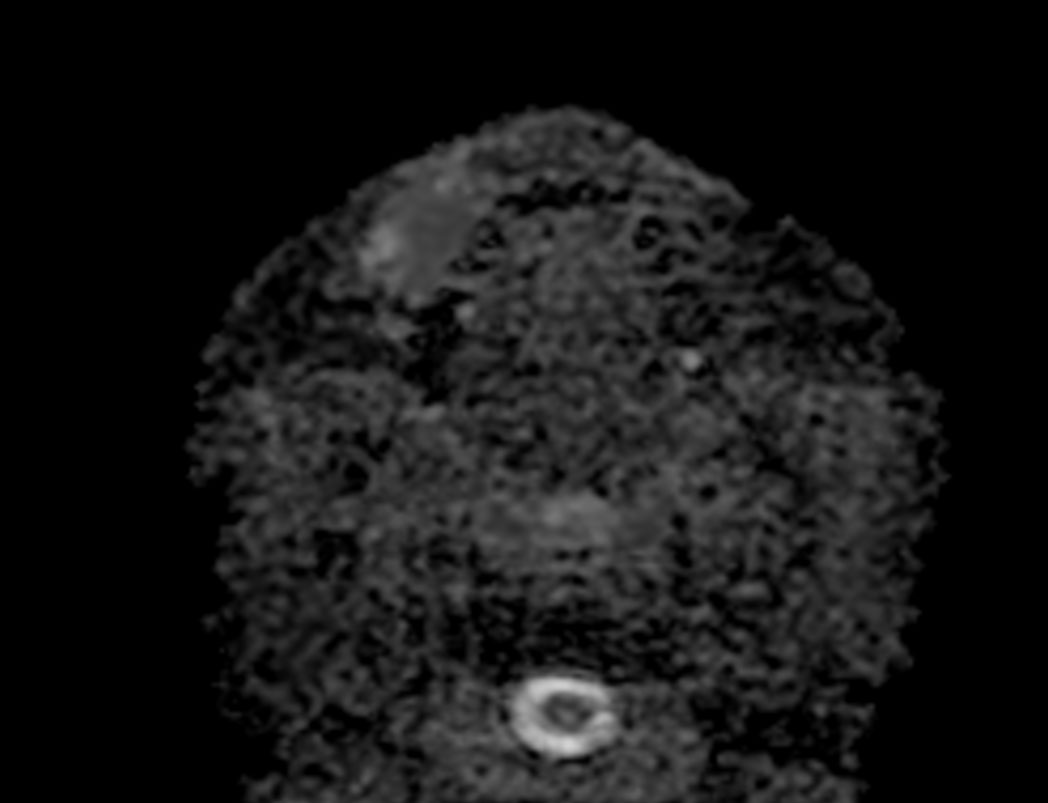

DWI TSE (b1000)